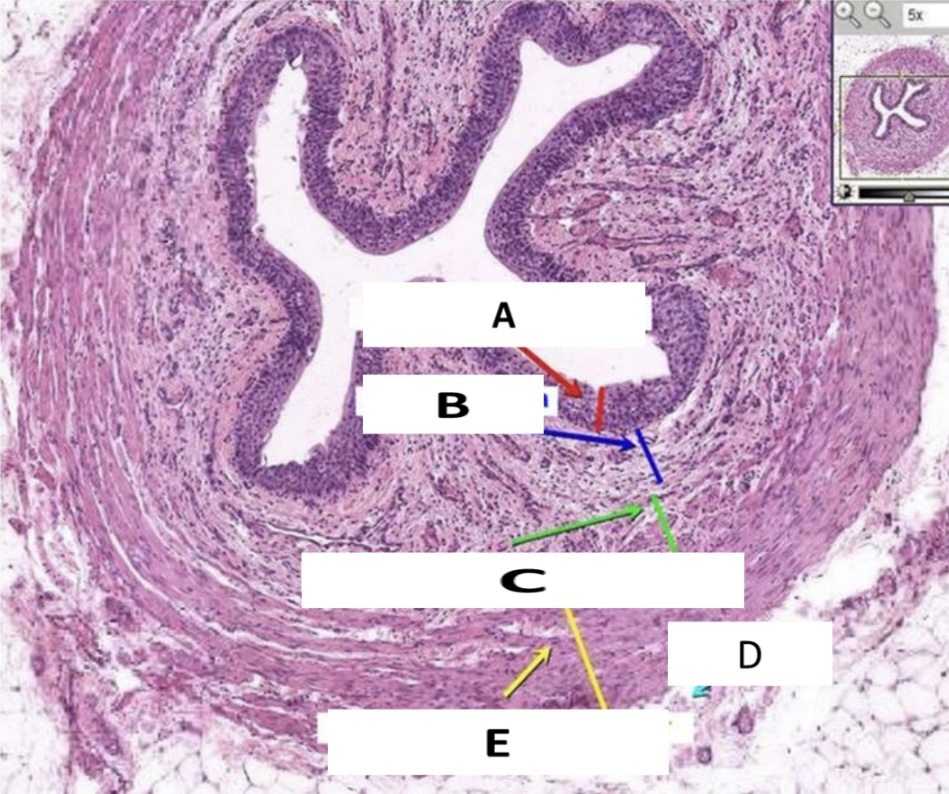

What organ is represented in the picture?

Ureter

Name the structure indicated by A.

Urothelium

Name the structure indicated by B.

Lamina propria

Name the structure indicated by C.

Lumen

Name the structure indicated by D.

Adventitia

Name the structure indicated by E.

Muscularis propria